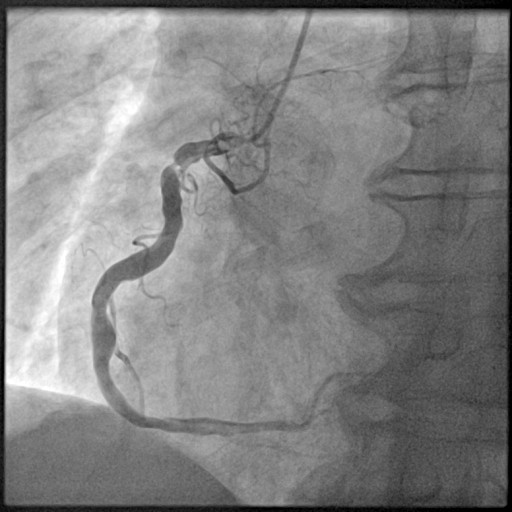

CORONAROGRAFIA

La Coronarografia è l’esame piu’ approfondito per valutare la presenza di restringimenti (“stenosi”) a carico delle arterie coronarie, ovvero delle arterie che nutrono il cuore. Viene effettuata tramite utilizzo di appositi cateteri che vengono inseriti attraverso l'arteria radiale o femorale. Per acquisire le immagini viene utilizzato un liquido chiamato “mezzo di contrasto” che opacizza il lume delle arterie mescolandosi al sangue. Le immagini vengono acquisite da un macchinario che emette una debole radiazione e registra le immagini.